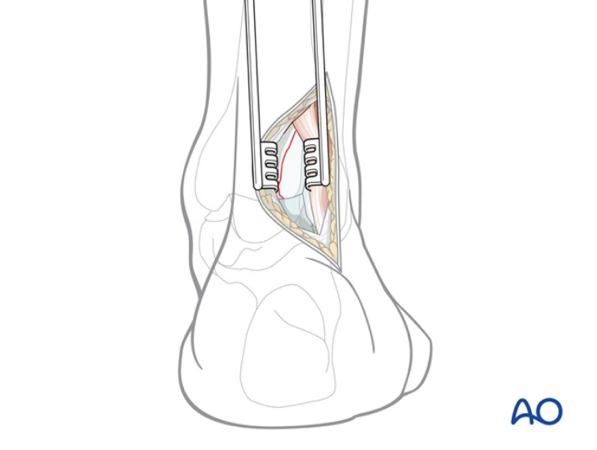

- Lateral Malleolus Fracture: Occurs when the distal portion of the fibula breaks, affecting the outer side of the ankle. This is the most common type of ankle fracture.

- Bimalleolar Fracture: This occurs when both the distal tibia and fibula are broken. It is the second most common type of ankle fracture.

- Trimalleolar Fracture: In this case, three parts of the ankle are fractured, most commonly involving the tibial malleolus, fibular malleolus, and posterior malleolus.